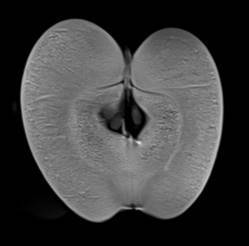

MRT-Aufnahmen eines Apfels

Der Aufsichtsratsvorsitzende der Klinikum Forchheim-Fränkische Schweiz gGmbH, Oberbürgermeister Dr. Uwe Kirschstein, und Landrat Dr. Hermann Ulm ließen sich vom Chefarzt der Radiologie, Dr. med. Hannes Seuß, die Eigenschaften dieses Neuzuganges erläutern. Die Funktionsweise demonstriert der Radiologe an einer Wassermelone. Hannes Seuß sagt: „Es ist keine Revolution der Bildgebung, sondern eine Evolution, der nächste große Schritt. Das Magnetfeld ist homogener, die Gradienten stärker und die Sequenzen vielfältiger. Dadurch entstehen aussagekräftigere Bilder und bessere Diagnosen.“

Die Magnetresonanztomografie, auch unter dem Namen Kernspintomographie bekannt, arbeitet ohne Röntgenstrahlen. Das MRT-System besteht aus einem großen Magneten, einer Antenne, die Radiowellen sendet und empfängt, und einem Computer, der die Signale in Bilder umwandelt und am Monitor darstellt. Die Auflösung dieser Bilder ist bei modernen Magnetresonanztomographen so hoch, dass selbst Stoffwechselvorgänge im Gehirn und anderen Organen sehr präzise untersucht werden können.

MRT-Aufnahmen von Apfel und Melone